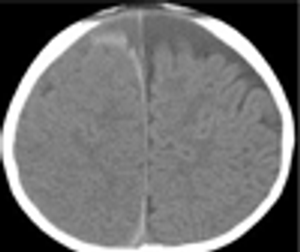

This 3 ½-month-old boy was brought to an outlying hospital after 12-hours of fussiness and poor feeding.